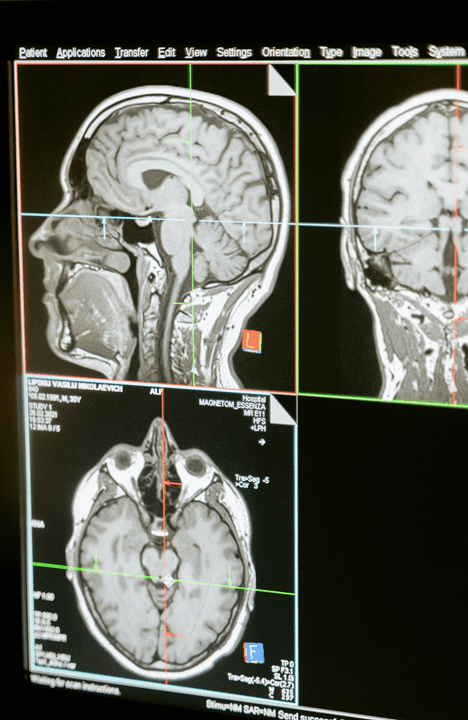

AI Medical Platform

By leveraging the same AI anomaly detection platform, process applications lend themselves to help medical diagnoses in detecting fractures, tumors, subtle abnormalities and patterns, reducing the risk of errors and enhancing diagnostic speed and accuracy.

The NextFind team has an incredible access to numerous hospitals and health care professionals across India thus our platform will be able to rapidly expand into many sectors of practice and conditions.

Continual learning in AI will have an immense effect on patient screening owing to its ability to improve the precision of diagnostics, greatly assisting in the early diagnosis of disease. These tools not only expedite processes, but strike a balance allowing medical professionals to identify and concentrate on complex cases requiring human expertise.